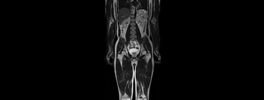

Lower Limb Angiography